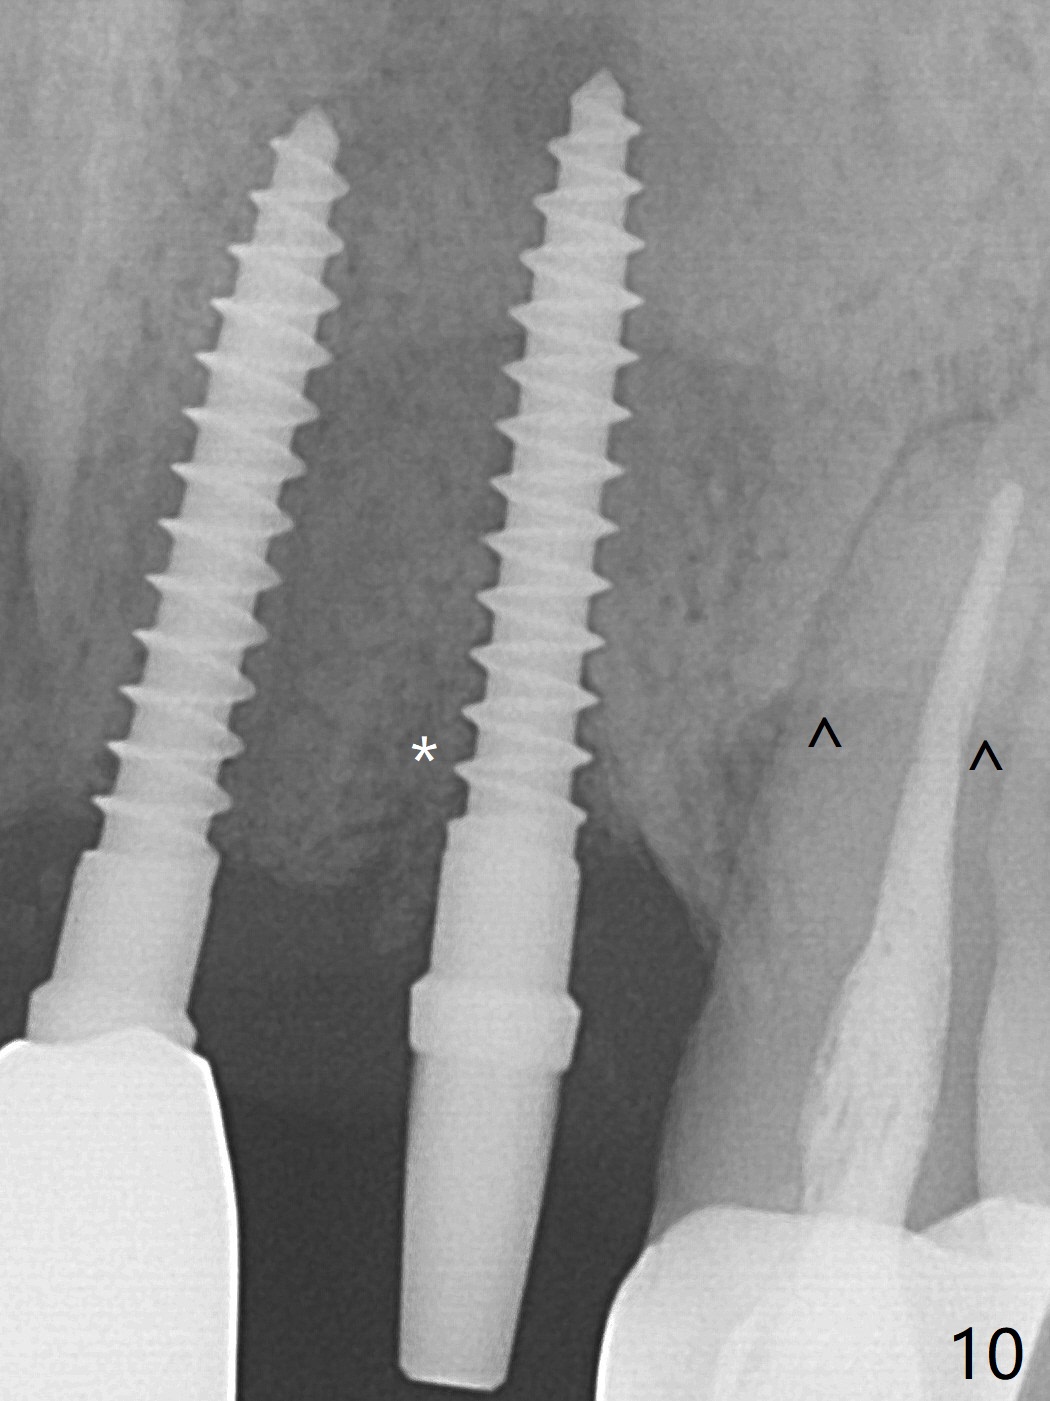

The tooth #10 has severe gingival recession (Fig.1) with loss of the buccal plate (Fig.2 *). After the initial osteotomy depth (Fig.3) increases by 2 mm, a 2.5x14(2) mm 1-piece implant is placed with insertion torque >60 Ncm (Fig.4). Palpation indicates the native bone apparently wider than CT shows. There is no sign of buccal or palatal plate perforation by palpation during osteotomy or implant placement. Vera Graft is placed repeatedly around the coronal threads (Fig.5-7 *). An immediate provisional is fabricated to close the socket (Fig.8). The buccal plate appears to collapse 1 month postop (cortical plate graft apparently more appropriate in this case); the margin of the provisional is trimmed so that the gingiva may grow incisally (Fig.9). The provisional dislodges several times postop due to short abutment. By nearly 4 months postop, the coronal bony defect seems to have been repaired (Fig.10 *). The tooth #11 has tenderness with bone loss (Fig.10 ^), corroborated by CT (distal bone loss, Fig.11 *). Since the apical bone is narrow (Fig.12), a narrow long implant is expected (Fig.13). Use an implant (3.5x13 mm) consistent with those at #14 and 15.